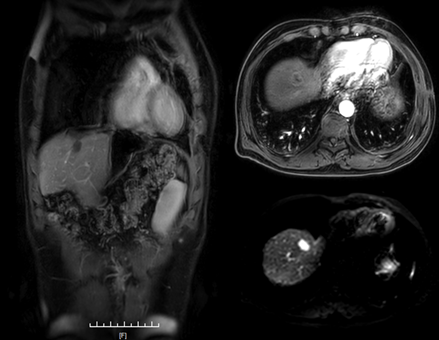

2018.6 肝脏MRI+C:肝左叶体积相对增大,肝裂增宽,肝内见多发异常信号影,大者直径约26mm,T1WI呈稍低信号,T2WI稍高信号,增强后环形强化。肝内、外胆管未见扩张。

2019.4 上腹部MR发现肝脏新发转移灶。

肝左叶缺如;肝裂增宽;右肝前上段近膈顶见一异常信号肿块,约15mm*20mm,T1WI呈稍低信号,T2WI稍高信号,增强后环形强化。右肝前上段近膈顶新发转移瘤。